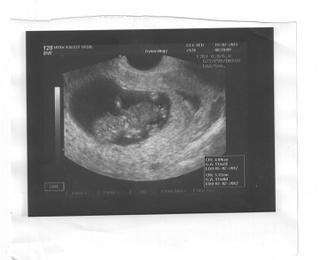

Ahojky . . . dlhise som tu nebola a tolko ste odvtedy popisali . . . Idem to rychlo precitat, aby som bola v obraze 🙂 Prikladam fotku nasho drobca z kontroly 19.7 - 11tt.

ahojte, dnes sme boli na NT, meriame 45,2 mm, NT 1,2, podľa ultrazvuku 11/2. sme v poriadku som taka stastna...este zajtra krv. juj tesím sa

ahojte, tak sme doma, vsetko v poriadku, babo ma 28 mm, sedi v tureckom sede, kruti furt rucickami a srdiecko mu bije ako zvon 😀 som sa po ceste domov usmievala ako leco 😀 😀 😀 dnes som videla dokocna mozog, je to neuveritelne.... a NT bolo nula, ale 10/2 je este skoro na meranie a mam aj fotku, zajtra v praci zoskenujem.